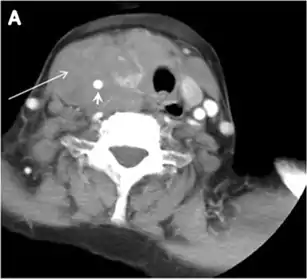

Fig. 8. A 48-year-old male patient post total thyroidectomy with PTC recurrence. a Transverse greyscale ultrasound of the neck demonstrates a left thyroid bed heterogeneous, predominantly hypoechoic irregular lesion with calcifications (white arrow). b A spot image of iodine 123 total body scan of the neck demonstrate a focus of abnormal radiotracer uptake at the left thyroid bed (Black arrows) between the annotated markers. c Enhanced axial CT scan of the neck demonstrates an enhancing large left thyroid bed mass (white arrow) with no calcifications. The lesion exerts a mass effect on the oesophagus (black arrow) and is inseparable from the trachea.[1]